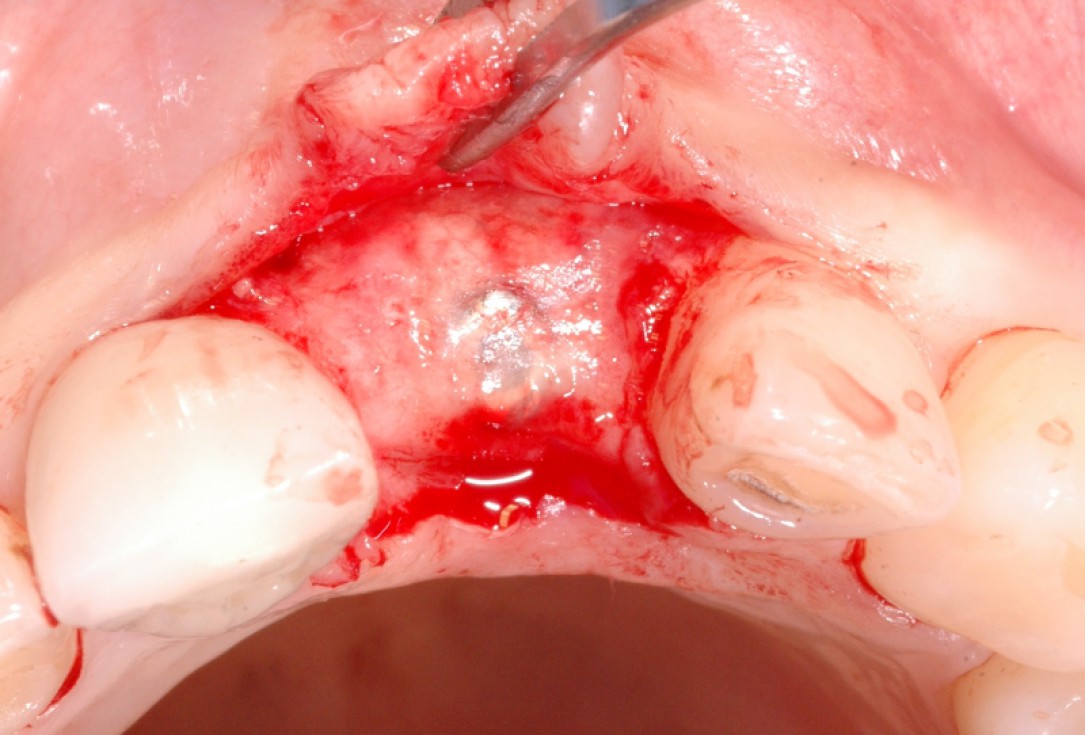

6/18 - Augmentation with maxresorb® and covering with a non-resorbable PTFE membraneGBR together with soft tissue augmentation with mucoderm® and maxresorb® - Dr. S. Scherg